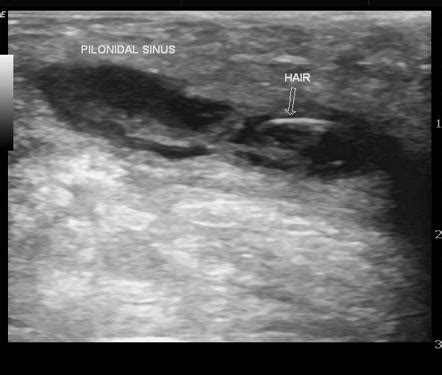

When it comes to imaging a pilonidal abscess , ultrasound is often the first tool in the radiologist’s toolkit, and for good reason, guys. It’s readily available, relatively inexpensive, and provides excellent real-time visualization of soft tissues, making it fantastic for detecting fluid collections like those pesky abscesses. The way ultrasound works is by bouncing sound waves off your body’s tissues and then interpreting the echoes to create an image. For a pilonidal abscess, the sonographer will use a transducer, which is like a wand, and apply a gel to the skin over the affected area. This gel helps to get good contact and transmit the sound waves effectively. As they move the transducer around, they’ll be looking for specific signs. The abscess itself typically appears as a well-defined, anechoic or hypoechoic area – basically, a dark or grayish area on the ultrasound screen, indicating a fluid-filled space. You might also see thickened walls around this collection, which signifies the body’s inflammatory response. The beauty of ultrasound is its ability to differentiate between solid and cystic structures. So, it can confirm that what they’re seeing is indeed an abscess filled with pus, rather than a solid tumor or other mass. Furthermore, ultrasound can help assess the size of the abscess, its depth, and its relationship to nearby structures, like muscles or blood vessels. This information is crucial for surgical planning, helping the surgeon decide on the best approach for drainage or excision. In some cases, ultrasound can even be used during the drainage procedure, guiding the needle precisely into the abscess cavity to ensure complete evacuation of the pus. This real-time guidance is a huge advantage. While ultrasound is great, it’s important to remember that it’s highly dependent on the skill of the sonographer and can sometimes be limited in obese patients or if there’s a lot of gas in the bowel overlying the area. But generally speaking, for initial evaluation and confirmation of a pilonidal abscess, ultrasound is a true workhorse in the radiology department.

So, when a radiologist looks at the images – be it an ultrasound, CT, or MRI – of a suspected pilonidal abscess , what are they specifically searching for? Guys, it’s like a detective hunt for clues! The primary goal is to confirm the presence of an abscess, which is essentially a collection of pus. On imaging, this typically appears as a well-defined area of fluid. In ultrasound , it’s often seen as a dark (anechoic) or mixed-echogenicity area with potentially thickened walls. On CT and MRI , these collections usually show up as areas of low signal intensity on certain sequences, often with a rim that enhances brightly after contrast administration, indicating inflammation. Another key thing radiologists look for is the size and extent of the abscess. Is it a small, localized collection, or is it a large, sprawling one? This information directly influences how it will be managed. They also assess its location relative to important anatomical structures. Is it superficial, or is it deep? Is it near the midline, or off to one side? This helps surgeons plan their approach. A critical finding, especially in recurrent cases, is the presence of sinus tracts . These are abnormal tunnels that can extend from the abscess or the original pit in the skin. Radiologists meticulously look for these tracts, as their identification is crucial for successful surgical treatment. They might appear as thin, linear areas of abnormal enhancement after contrast. The radiologist will describe the course, length, and any branching of these tracts. Finally, they are on the lookout for associated findings that might indicate a more complex situation. This could include surrounding inflammation of the skin and subcutaneous tissues (cellulitis), evidence of bone infection (osteomyelitis, though rare), or other rare complications. Interpreting these findings requires a deep understanding of both anatomy and pathology, making the radiology report a vital piece of the puzzle for the treating physician managing the pilonidal abscess . The radiologist’s detailed description helps paint a clear picture, guiding the clinician towards the most appropriate and effective treatment strategy for the patient.